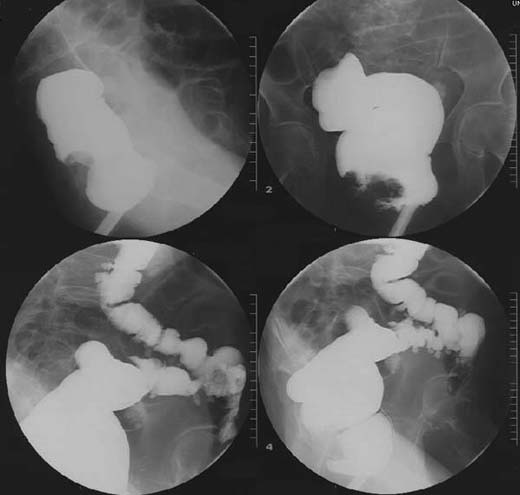

Patient mit Blutung peranal.

Multiple

Kontrastmittel-gefüllte

Ausstülpungen der Dickdarmwandung des Colon sigmoideum. Breitbasige

Raumforderung bzw. Kontrastmittel-Aussparung des Rectums.

Rectum-Karzinom

Rectum-Adenom